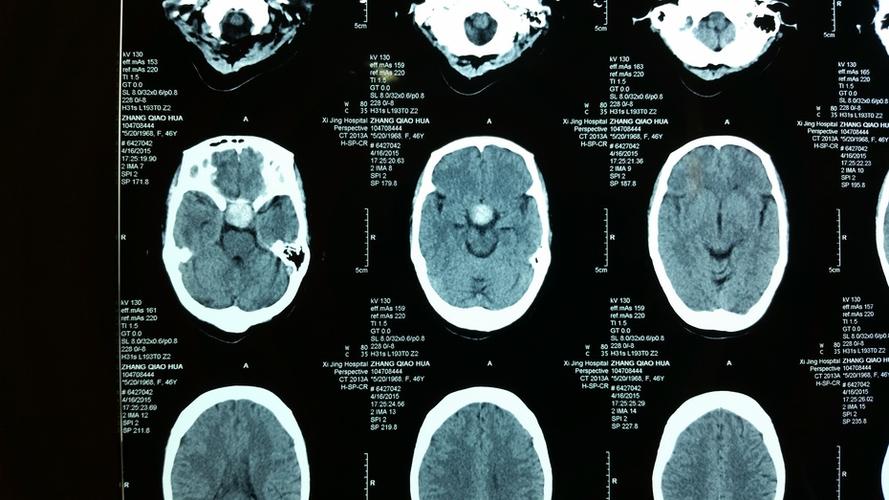

头颅ct检查提示:鞍区可见一类圆形稍高密度影,边界清晰锐利,以宽基底

头颅ct可见鞍区类圆形高密度影

经检查ct:鞍区占位,密度混杂,鞍底骨质破坏,向蝶窦内发展 视力检查